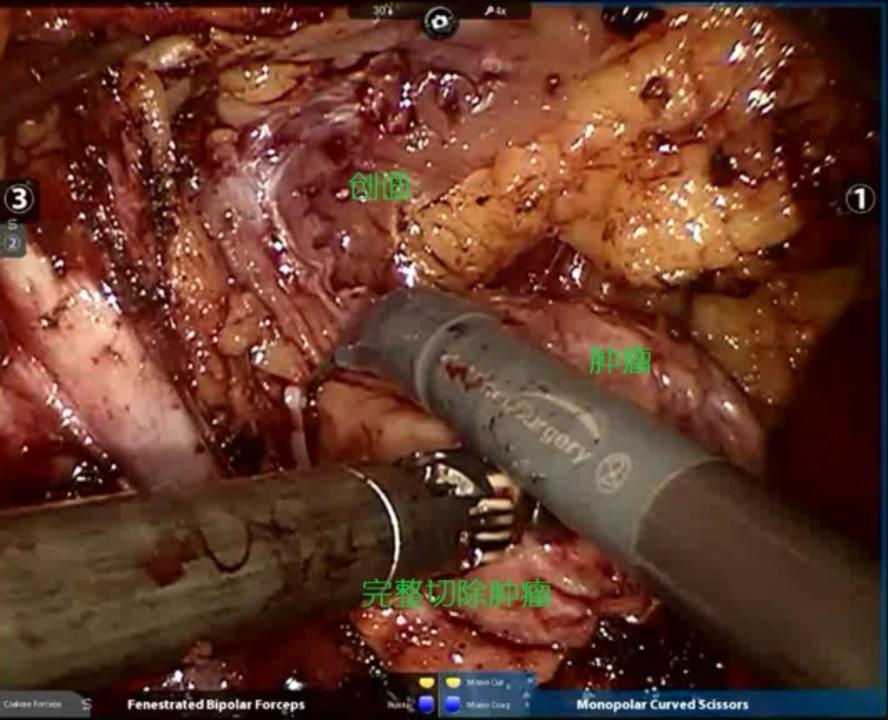

3.切除肿瘤:阻断肾动脉后,选择肿瘤边界稍清晰的一边入手,切开粘连的肾周脂肪,显露肾实质及肿瘤边界,逐层切开寻及肿瘤包膜,沿包膜完整剥除肿瘤。